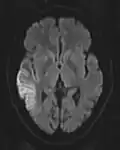

The most common application of conventional DWI (without DTI) is in acute brain ischemia. DWI directly visualizes the ischemic necrosis in cerebral infarction in the form of a cytotoxic edema,[38] appearing as a high DWI signal within minutes of arterial occlusion.[39] With perfusion MRI detecting both the infarcted core and the salvageable penumbra, the latter can be quantified by DWI and perfusion MRI.[40]

DWI showing necrosis (shown as brighter) in a cerebral infarction -

Cerebral infarction leads to diffusion restriction, and the difference between images with various DWI weighting will therefore be minor, leading to an ADC image with low signal in the infarcted area.[24] A decreased ADC may be detected minutes after a cerebral infarction.[26] The high signal of infarcted tissue on conventional DWI is a result of its partial T2 weighting.[27]